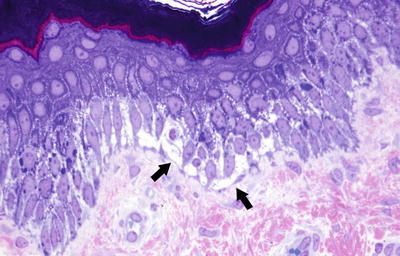

3.3.2 Histology

Fig. 3.8

Rare acantholytic cells can be seen at the base of the separation in Staphylococcal scalded skin syndrome